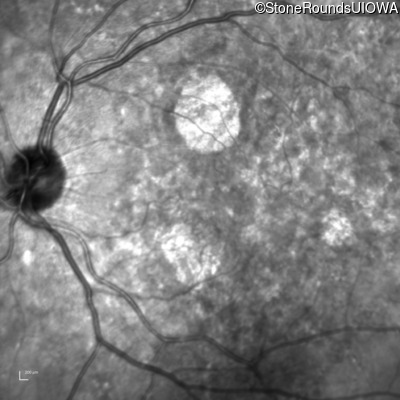

Infrared Fundus Photograph - Right - 20/25 +2

Exemplar

Infrared Fundus Photograph - Left - 20/20 -2